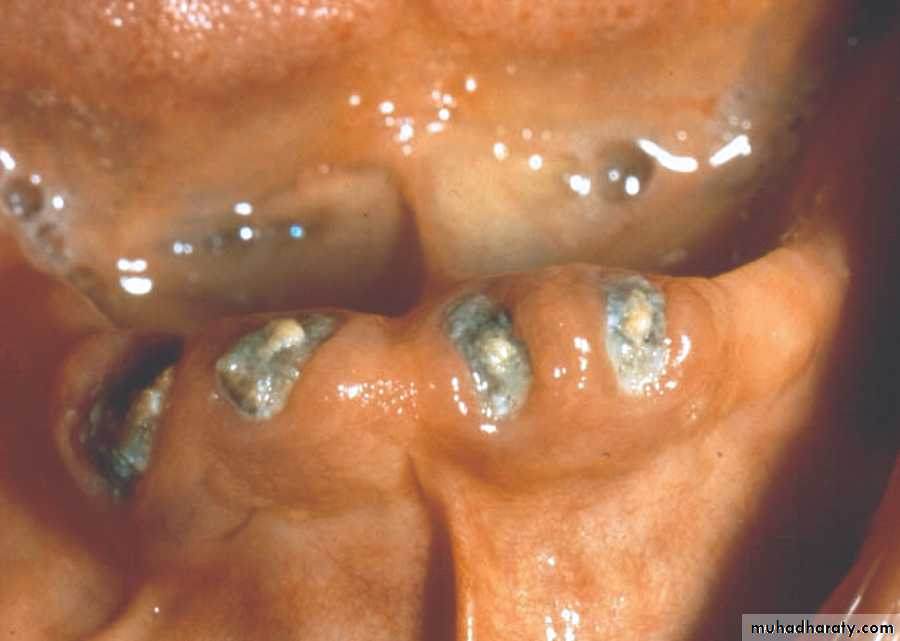

Retained dentition (un erupted, R.Root) associated with pathology….asymptomatic for years, may increase bone loss, impact upper third molar…preserve tuberosity .

Removal of pathogenic bony conditions

( cyst, tumors)Cyst:…...enucleating or marsupialization